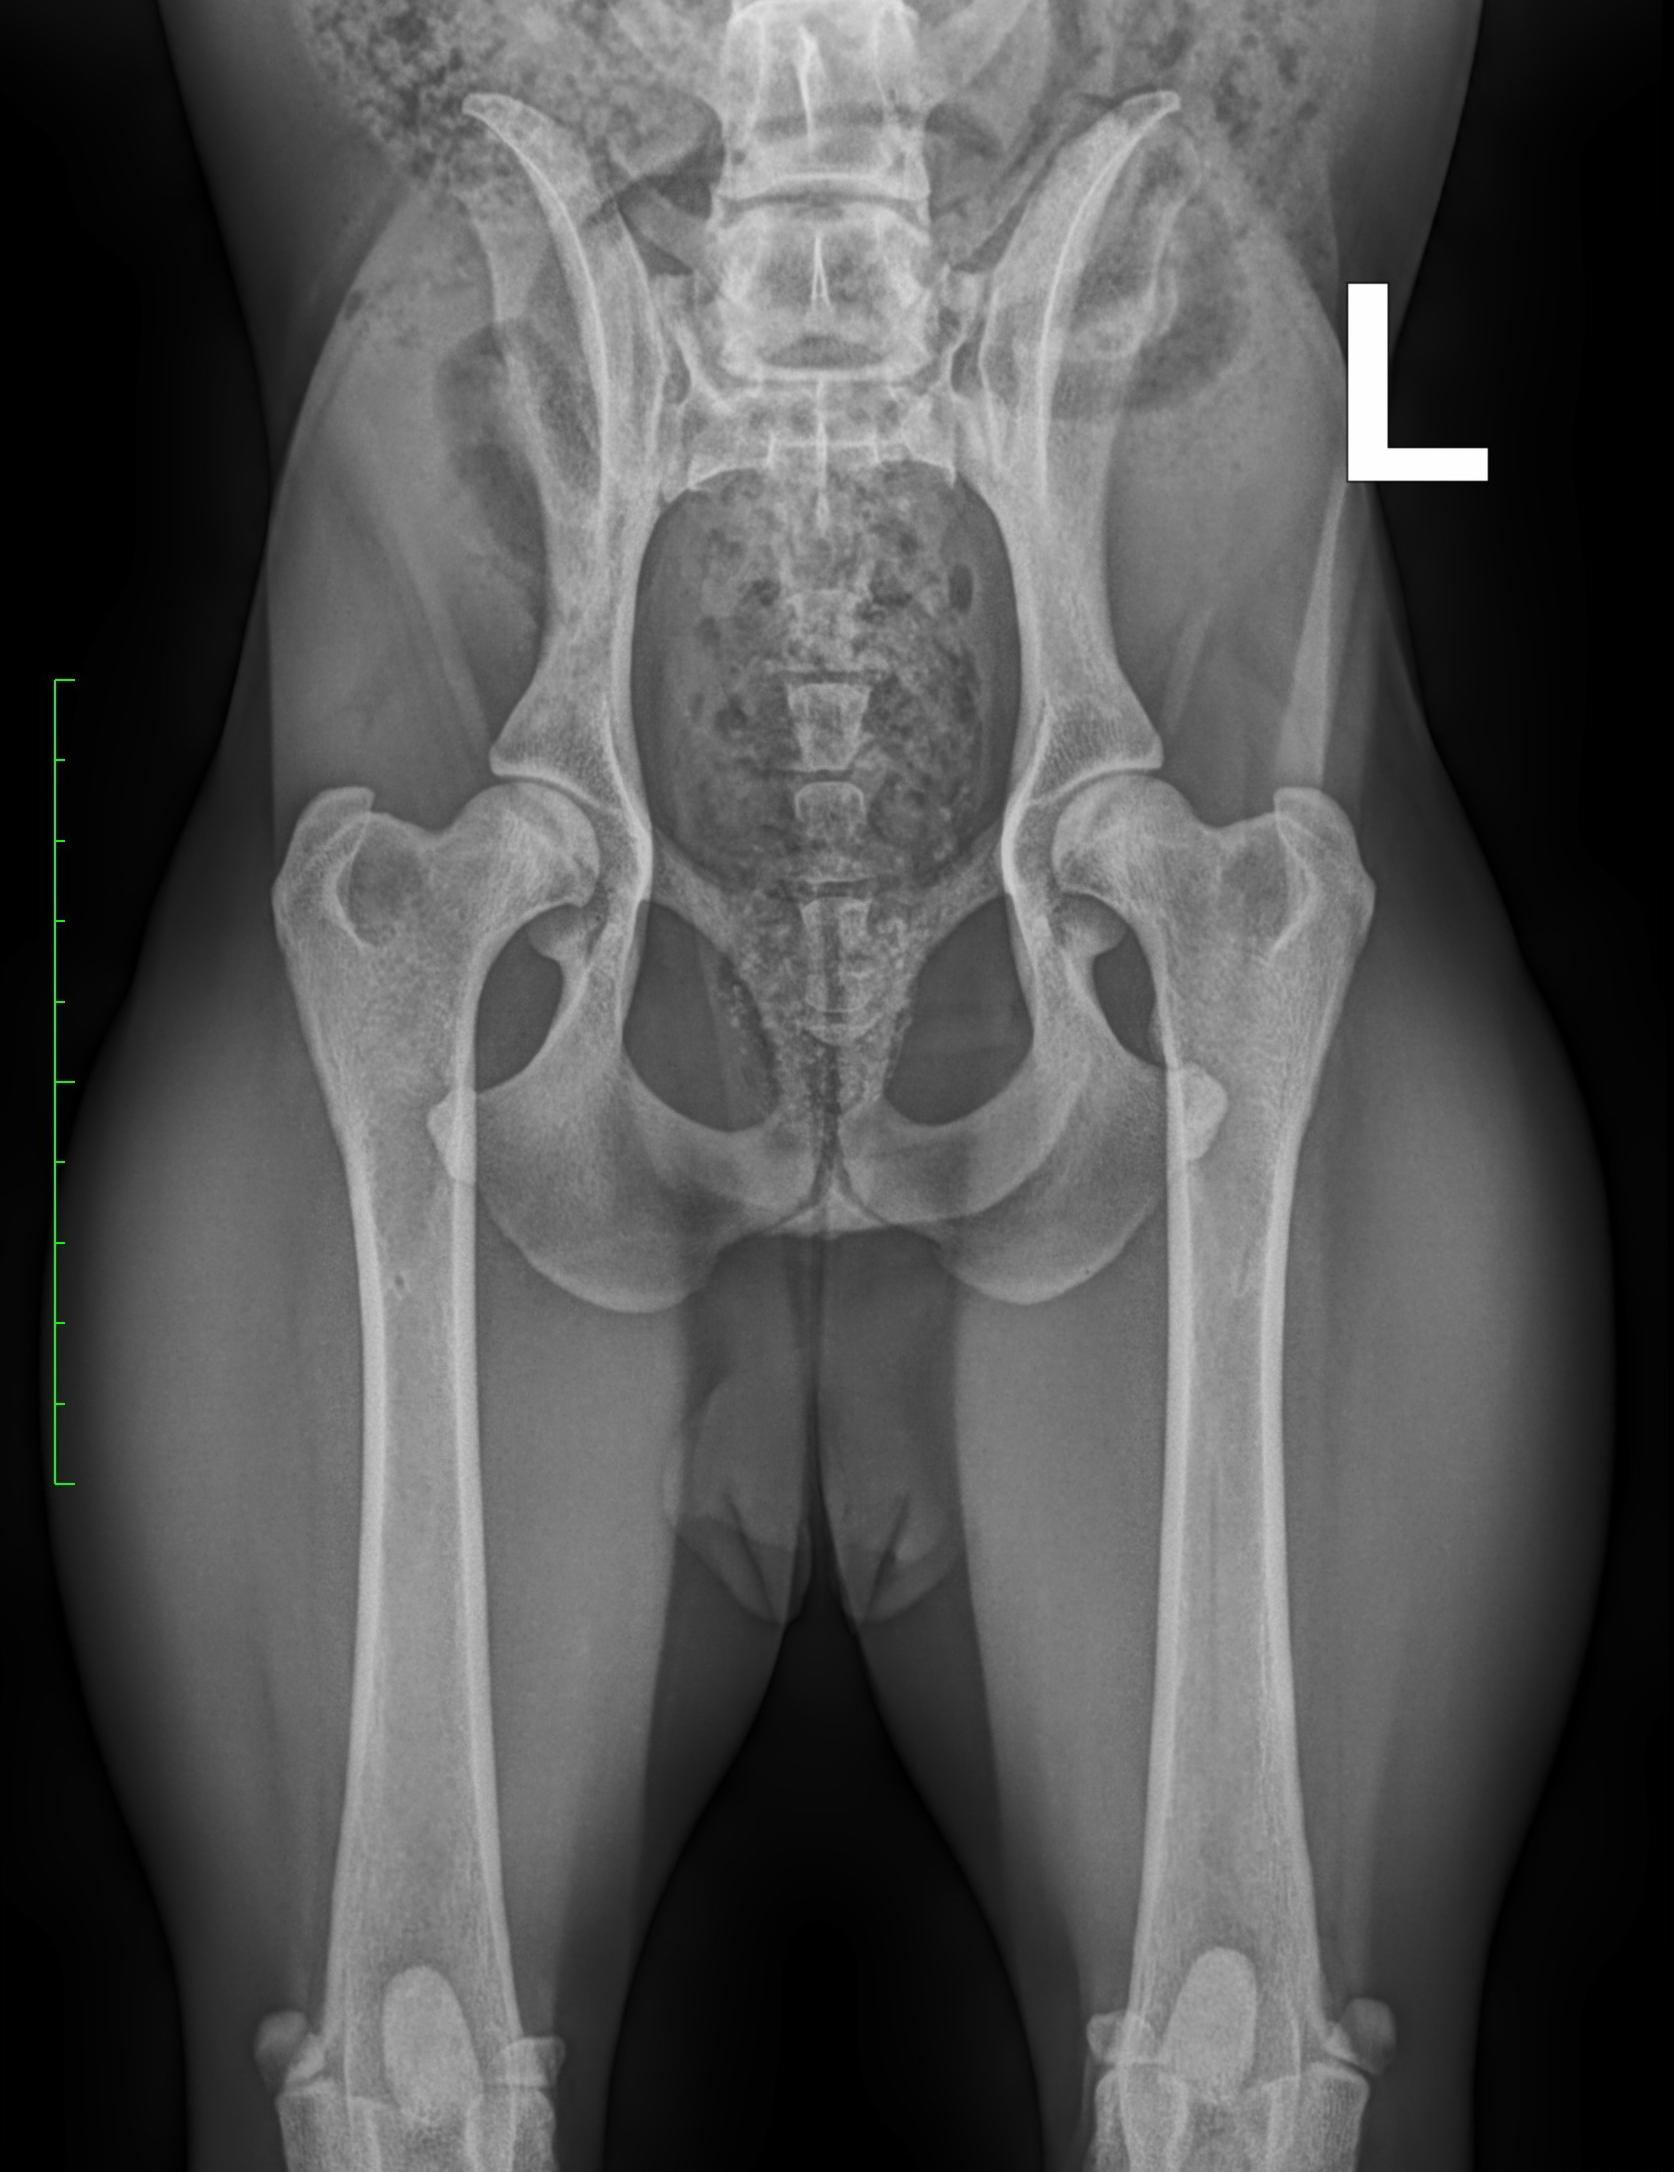

Dysplasie de la hanche